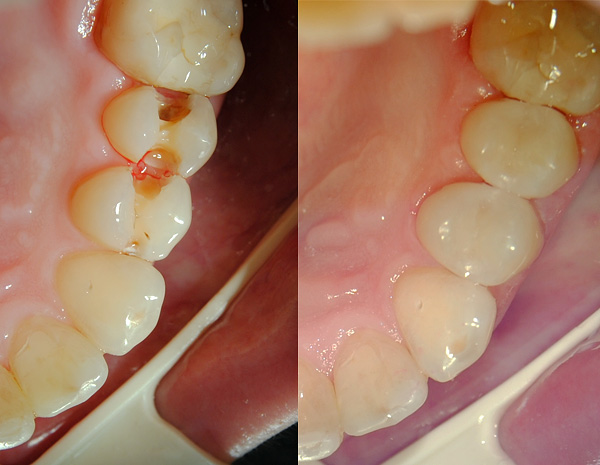

A foto abaixo mostra a cárie média localizada na região da fissura (fossa) dos molares:

Em casa, esses defeitos nem sempre podem ser identificados corretamente - eles podem parecer manchas acinzentadas ou marrons, pontos, ranhuras. Se esse defeito estiver no espaço interdental, pode ser difícil perceber. Defeitos nos molares pequenos e grandes inferiores são claramente visíveis (um exemplo é dado na fotografia abaixo).

Às vezes, as queixas de dor podem não estar presentes, mas a aparência de pontos cariados muda para pior a cada mês - e este é um indicador de 100% de defeitos não adquiridos, mas adquiridos, ou seja, cárie. Somente o dentista pode esclarecer o estágio do processo cariado, coletando informações adicionais: especificando o histórico médico, examinando a cavidade oral e sondando o dente cariado. Às vezes, métodos instrumentais de pesquisa (diagnóstico por raios X, EDI) também podem ser aplicados.